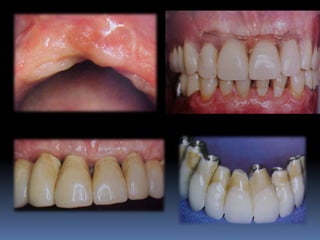

Guia estético

•Simulação da prótese a ser confeccionada,

informando durante planejamento as

possibilidades protéticas ao paciente

(consentimento e colaboração)

•Com o auxílio de fotografias dão noção exata

de como ficará a prótese

•Suporte de lábio superior visualizado com

enceramento

•Necessidade de cirurgias reconstrutivas tais

como enxertos ósseos, gengivais e distrações

osteogênicas

•Alinhamento, desgastes e plano articular e

oclusal em relação ao rebordo alveolar